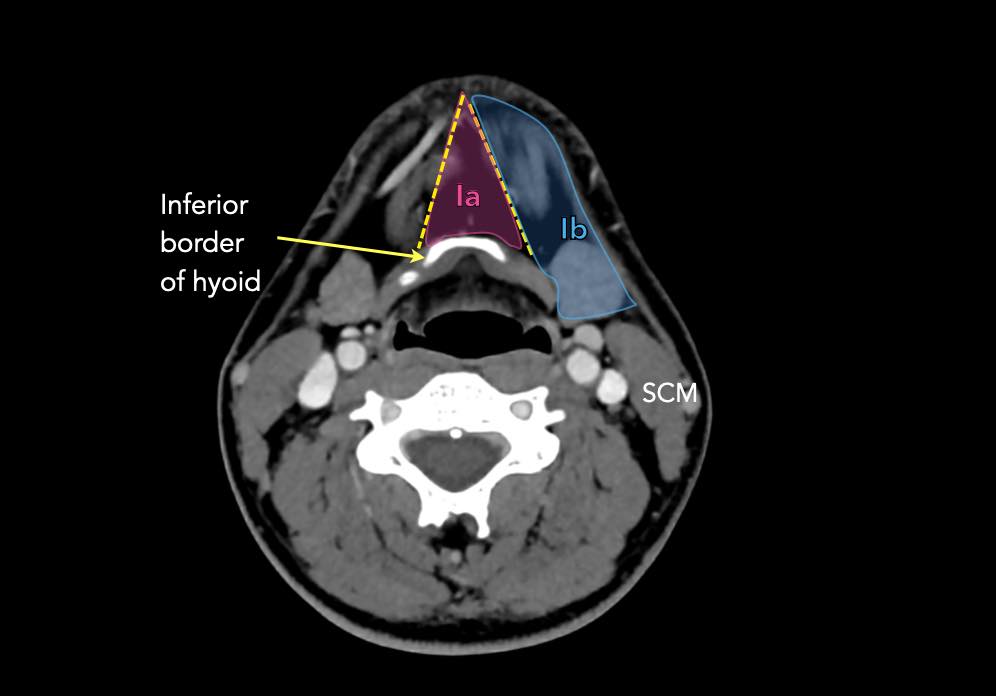

I – Dưới cằm và dưới hàm

Các hạch bạch huyết ở tầng I có nguy cơ phát triển di căn từ các ung thư khoang miệng, hốc mũi trước, mô mềm vùng mặt giữa và tuyến dưới hàm.

Tầng Ia

là vùng giữa nằm giữa bụng trước của các cơ nhị thân, chứa các hạch dưới cằm.

Tầng Ib

chứa các hạch dưới hàm nằm trong khoang giữa mặt trong của xương hàm dưới ở phía ngoài và cơ nhị thân ở phía trong, từ khớp mu cằm ở phía trước đến tuyến dưới hàm ở phía sau.